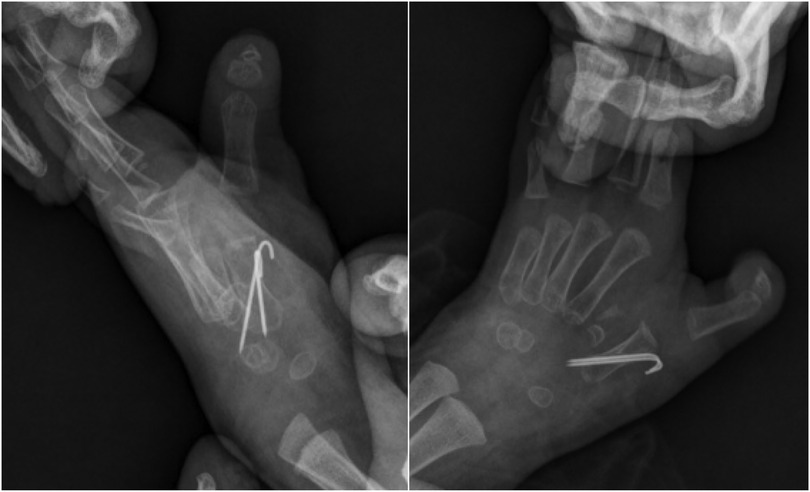

Abstract Congenital anomalies of the hand and forearm present a complex challenge in plastic and pediatric surgery. We present the case of a 13-month-old child with a congenital left mirror deformity, characterized by the presence of eight digits and two ulnae exhibiting near-perfect bilateral symmetry. A novel palmar-based incision design was employed for the corrective and functional reconstruction of the left hand,which may serve as a reference for the surgical management of similar conditions. Preoperatively, the radial-side middle finger demonstrated palmar opposition against the ulnar aspect of the palm.The surgical procedure included resection of the radial-sided index, ring, and little fingers , along with pollicization of the middle finger. Functional reconstruction of the neothumb involved restoring adduction and abduction using preserved native anatomical structures. Following comprehensive clinical and imaging evaluations, the patient underwent successful surgical treatment.Postoperatively, substantial improvements were observed in both hand morphology and grasping function. Through our novel palmar incision approach, we effectively reconstructed thumb opposition and adduction while preserving intrinsic hand musculature and achieving optimal scar concealment. In managing mirror hand deformities, meticulous selection of the most dominant digit for thumb reconstruction remains crucial. At the initial surgical stage, osteotomy of the selected digit was performed to enhance its morphological similarity to a normal thumb.